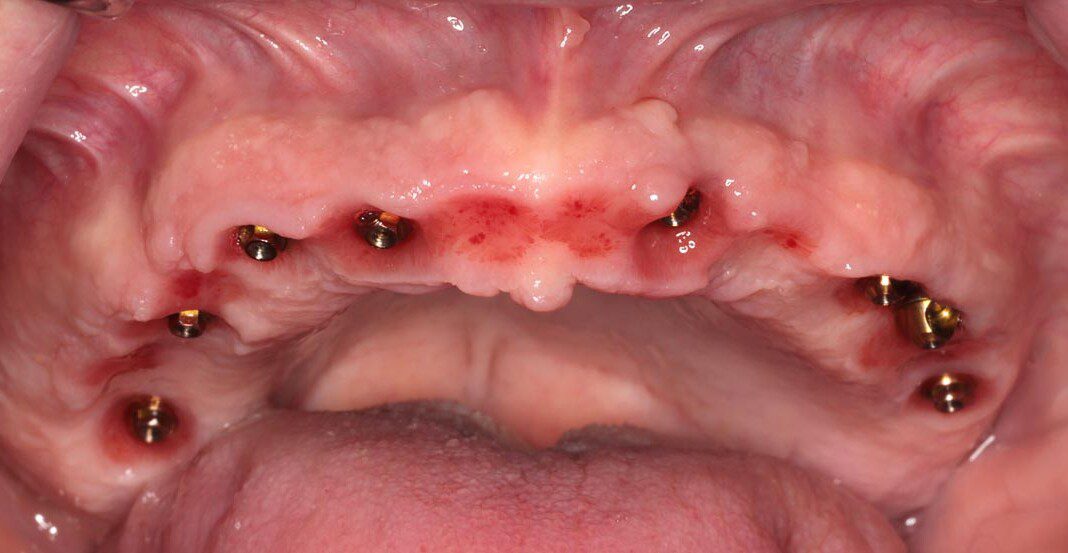

Three months post, first surgery the patient returns for implant uncovering and these are the impression copings preparing for the fixed temporary bridge.